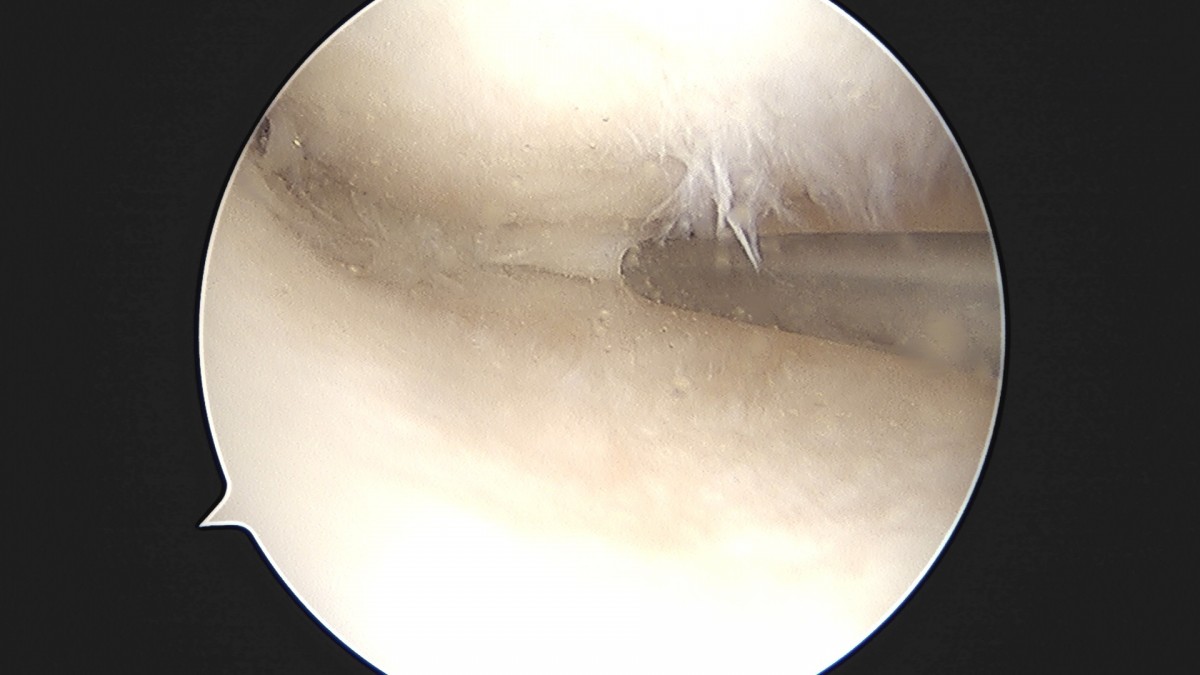

이재상원장님 무릎 반월상 연골판 절제술 박민O 환자

dae765e4d9ac96aee867c9d6292d8784_1758005184_1135.jpg